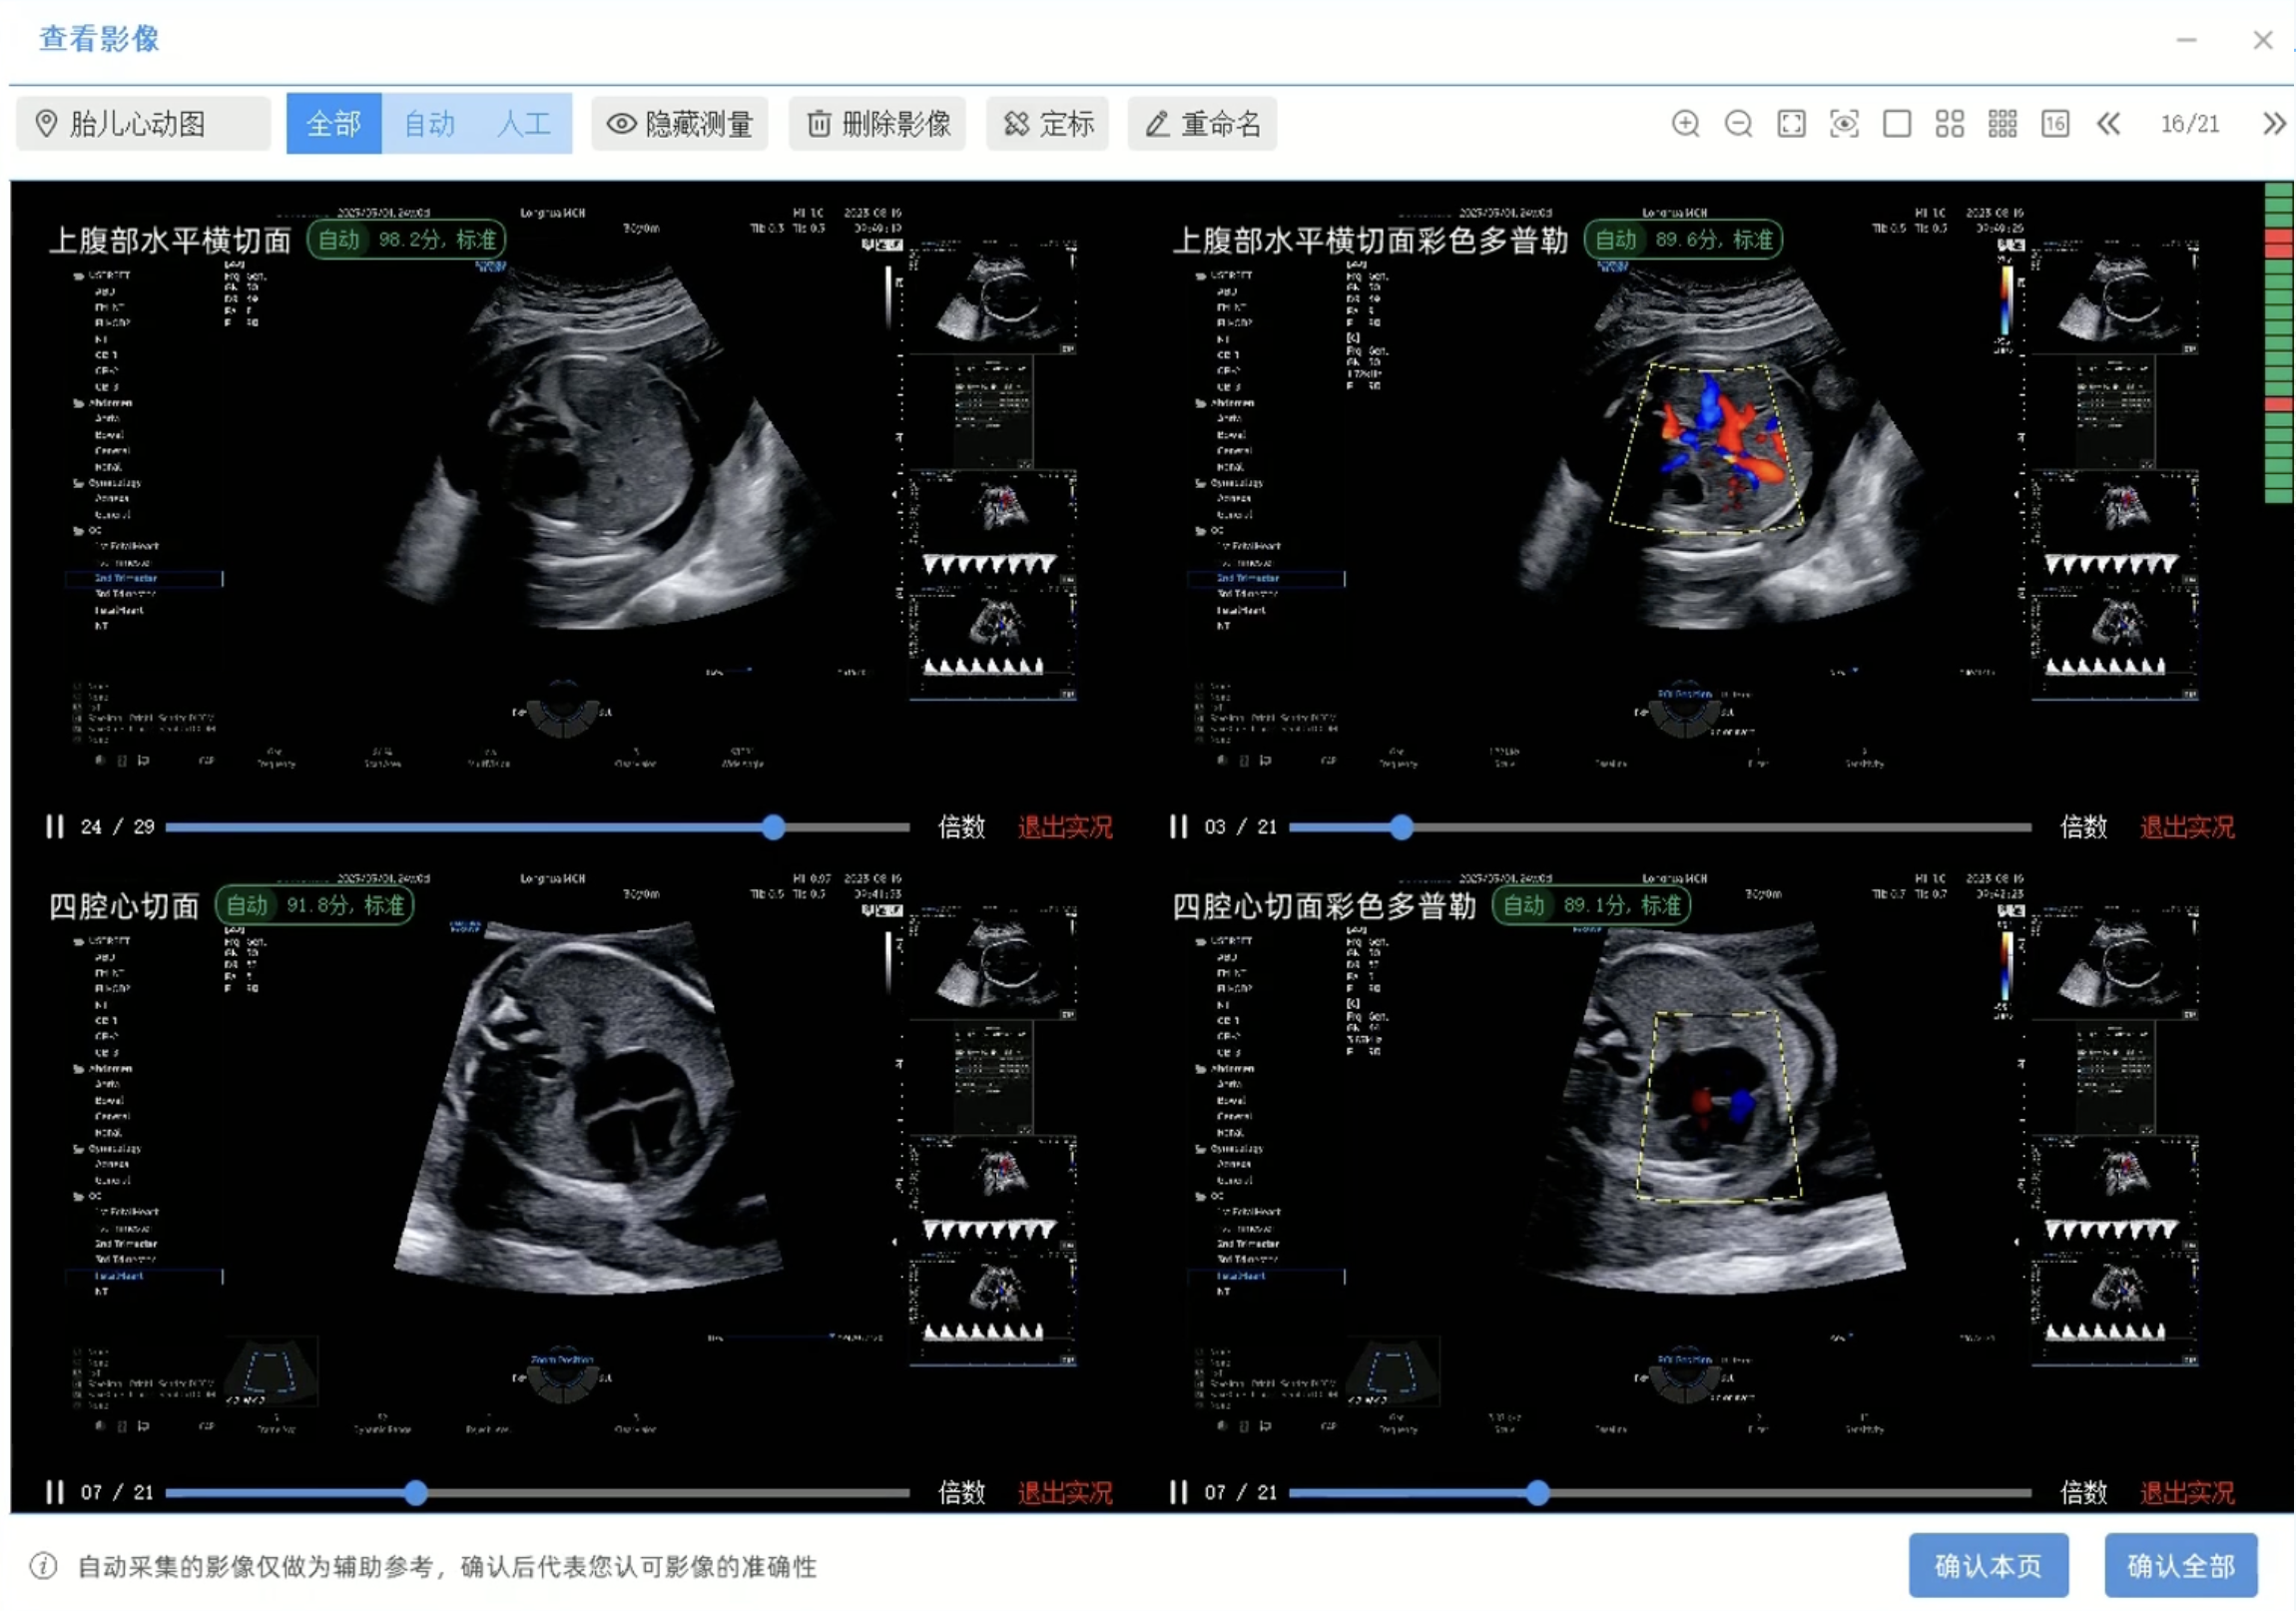

事中实时质控是核心竞争力。扫查过程中影像实时评分及最优切面智能替换,将传统时候质控优化为事中实时质控,为每一例筛查筑牢质量防线。

“标准短视频”智能留存